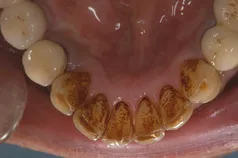

[症例1]

歯石除去だけでは取りきれないタバコのヤニなどのステインもエアーフローという機械を用いて除去しています。

• 治療期間:1ヶ月

• 治療費:保険適応内治療

• 治療回数:3回